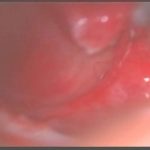

手術前2